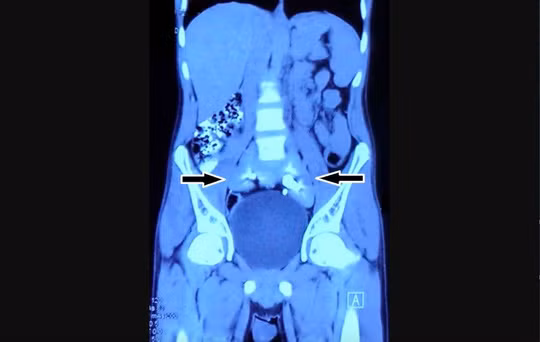

| Trẻ em mắc bệnh tay chân miệng nhập viện tăng đột biến. |

Trong khi đó, ông Nguyễn Đình Tuyến, Giám đốc Bệnh viện sản nhi Quảng Ngãi, cho hay đơn vị tiếp nhận điều trị các ca bệnh ở độ 2B trở lên; bố trí khu cách ly tuyệt đối với các bệnh nhân đang điều trị các bệnh khác tại bệnh viện.

“Hiện bệnh viện chỉ có 500 giường nhưng số ca bệnh tay chân miệng tăng đột biến, lúc điểm cao lên đến 131 ca mỗi ngày nên quá tải. Bệnh nhân mắc bệnh tay chân miệng ở cấp độ 4 phải có máy để lọc máu nhưng bệnh viện chưa có. Do đó, các bệnh nhân nặng phải chuyển lên tuyến trên”, ông Tuyến nói.